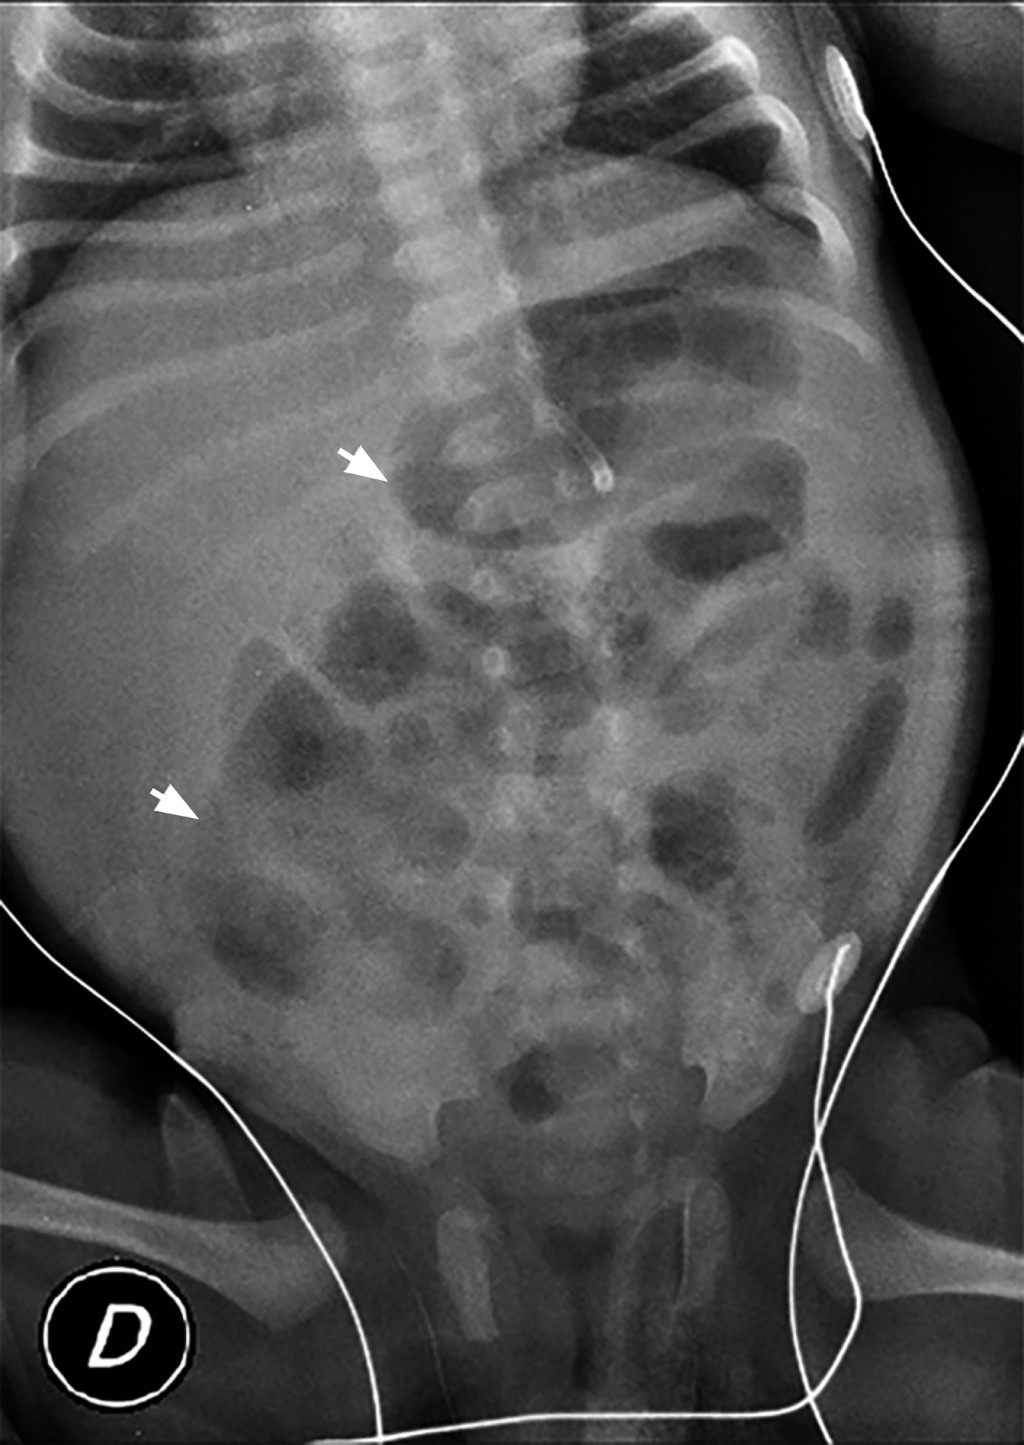

Un día después del nacimiento, presenta distensión abdominal y ausencia de evacuaciones, por lo que se toma radiografía simple de abdomen (Figura 1) donde se evidencian asas intestinales distendidas y ausencia de aire en ámpula rectal. Se traslada a unidad de cuidado intensivo neonatal (UCIN) por sospecha de obstrucción intestinal y sepsis neonatal; se inicia nutrición parenteral total (NPT), colocación de sonda orogástrica y manejo antibiótico. Se realizan enemas evacuantes con solución salina al 0.9%, sin obtener evacuación.

Figura 1